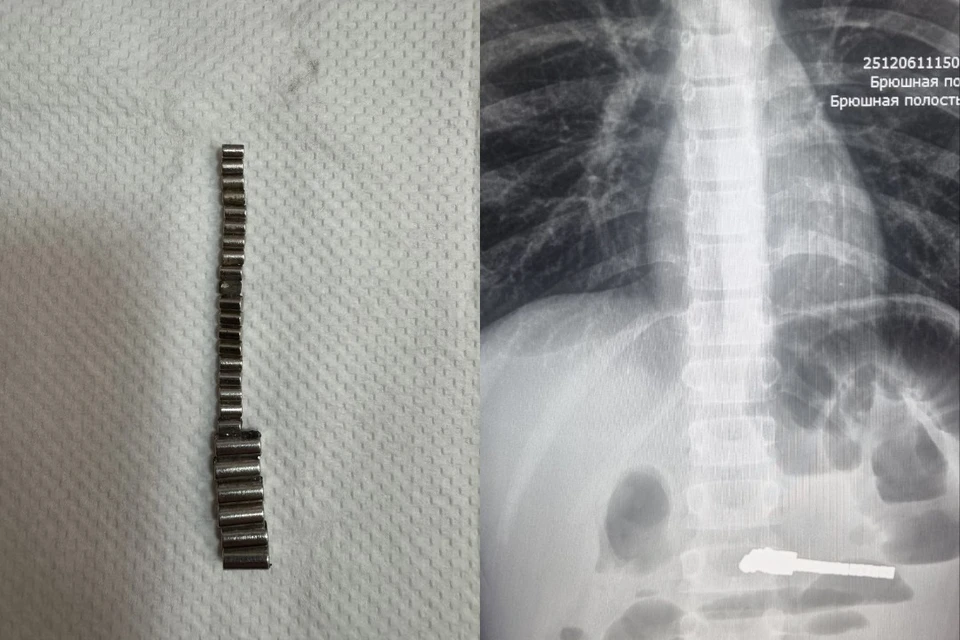

Страшную картину увидели врачи на снимке: в животе маленького пациента, который поступил в больницу с сильнейшими болями и рвотой, скопилось множество посторонних предметов. Ребёнку срочно требовалась операция. И когда хирурги начали её, они ахнули: из кишечника малыша один за другим они извлекли 25 маленьких магнитов.

У мальчика длительное нахождение 25 магнитов в ЖКТ привело к серьёзным осложнениям. Это была экстренная ситуация.